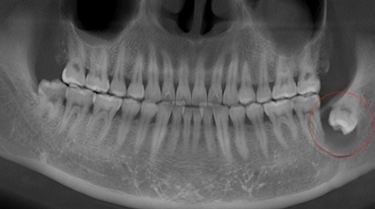

Dientes impactados

Los dientes impactados son dientes que no pueden erupcionar correctamente debido a la falta de espacio o a una obstrucción.

Los pacientes pueden notar que un diente no ha salido, aunque debería haberlo hecho. Esta condición es común con las muelas del juicio y los caninos superiores.

El tratamiento puede incluir la extracción del diente impactado o la creación de espacio para permitir su erupción.